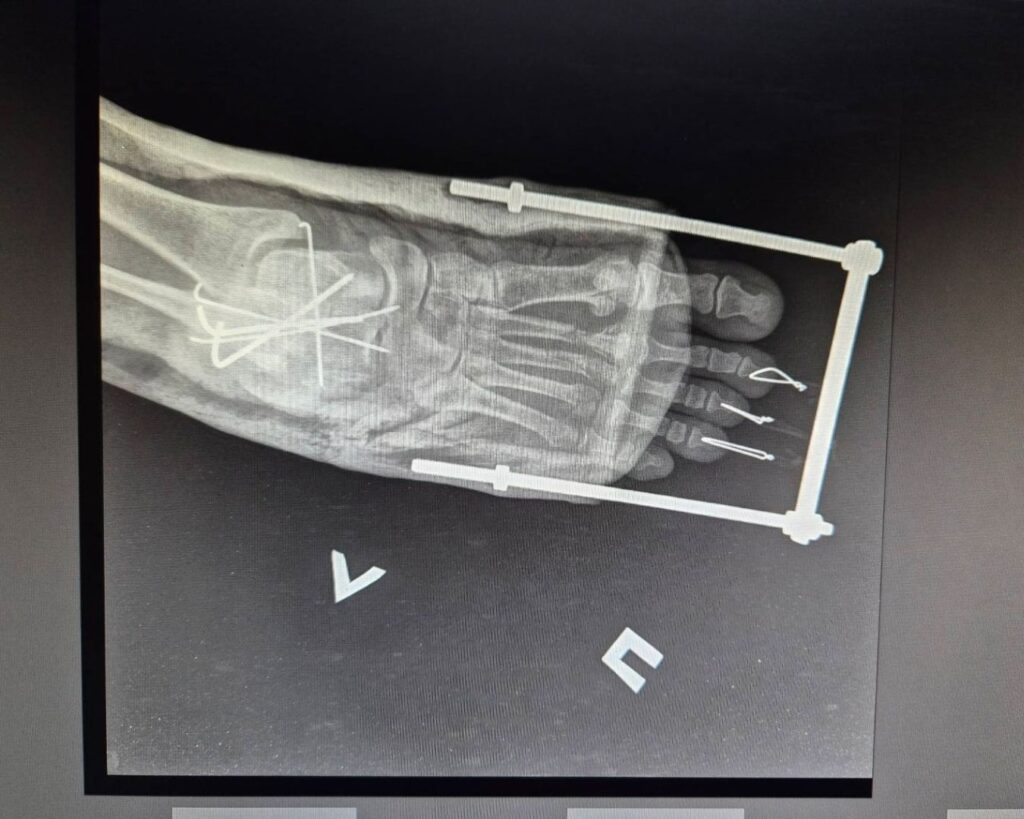

“One of the patients is a female medical worker who was returning home from her shift when the drone struck the bus,” says Olha Severyn, MSF anesthesiologist at the hospital in Kherson. “She suffered severe injuries to her legs and feet. We provided anesthesia and performed surgery.” Another patient arrived with a serious leg fracture and significant blood loss and received timely treatment. Both women are currently in stable condition.

Patients told MSF staff that the drone dropped explosives that detonated under the vehicle, causing many people to suffer injuries to their lower limbs.